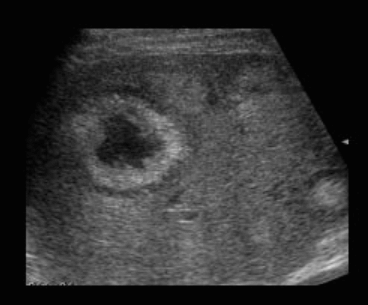

- bull's eys sign (종양 변연에 중심부가 고에코이고 경계부가 저에코인 두꺼운 띠가 보인다)

- cluster sign (종양이 융합하여 분엽모양을 이루어 마치 포도송이 모양을 나타낸다)